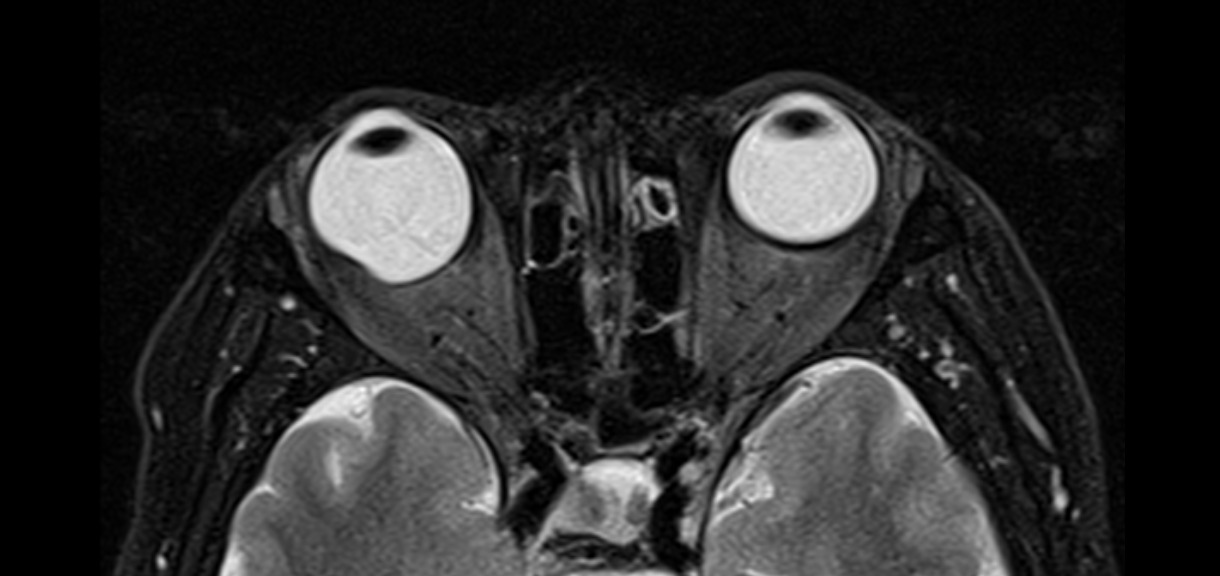

Cortes axiales de resonancia magnética de órbitas en el cual se aprecia aumento del tamaño del globo ocular derecho a expensas de su eje anteroposterior, acompañado de adelgazamiento de su pared posterior lo cual corresponde a estafiloma.

Definición: Adelgazamiento y estiramiento de las capas escleral-uveal del globo ocular.

Hallazgos por imagen: Aumento del tamaño del globo ocular y adelgazamiento de sus paredes posteriores.